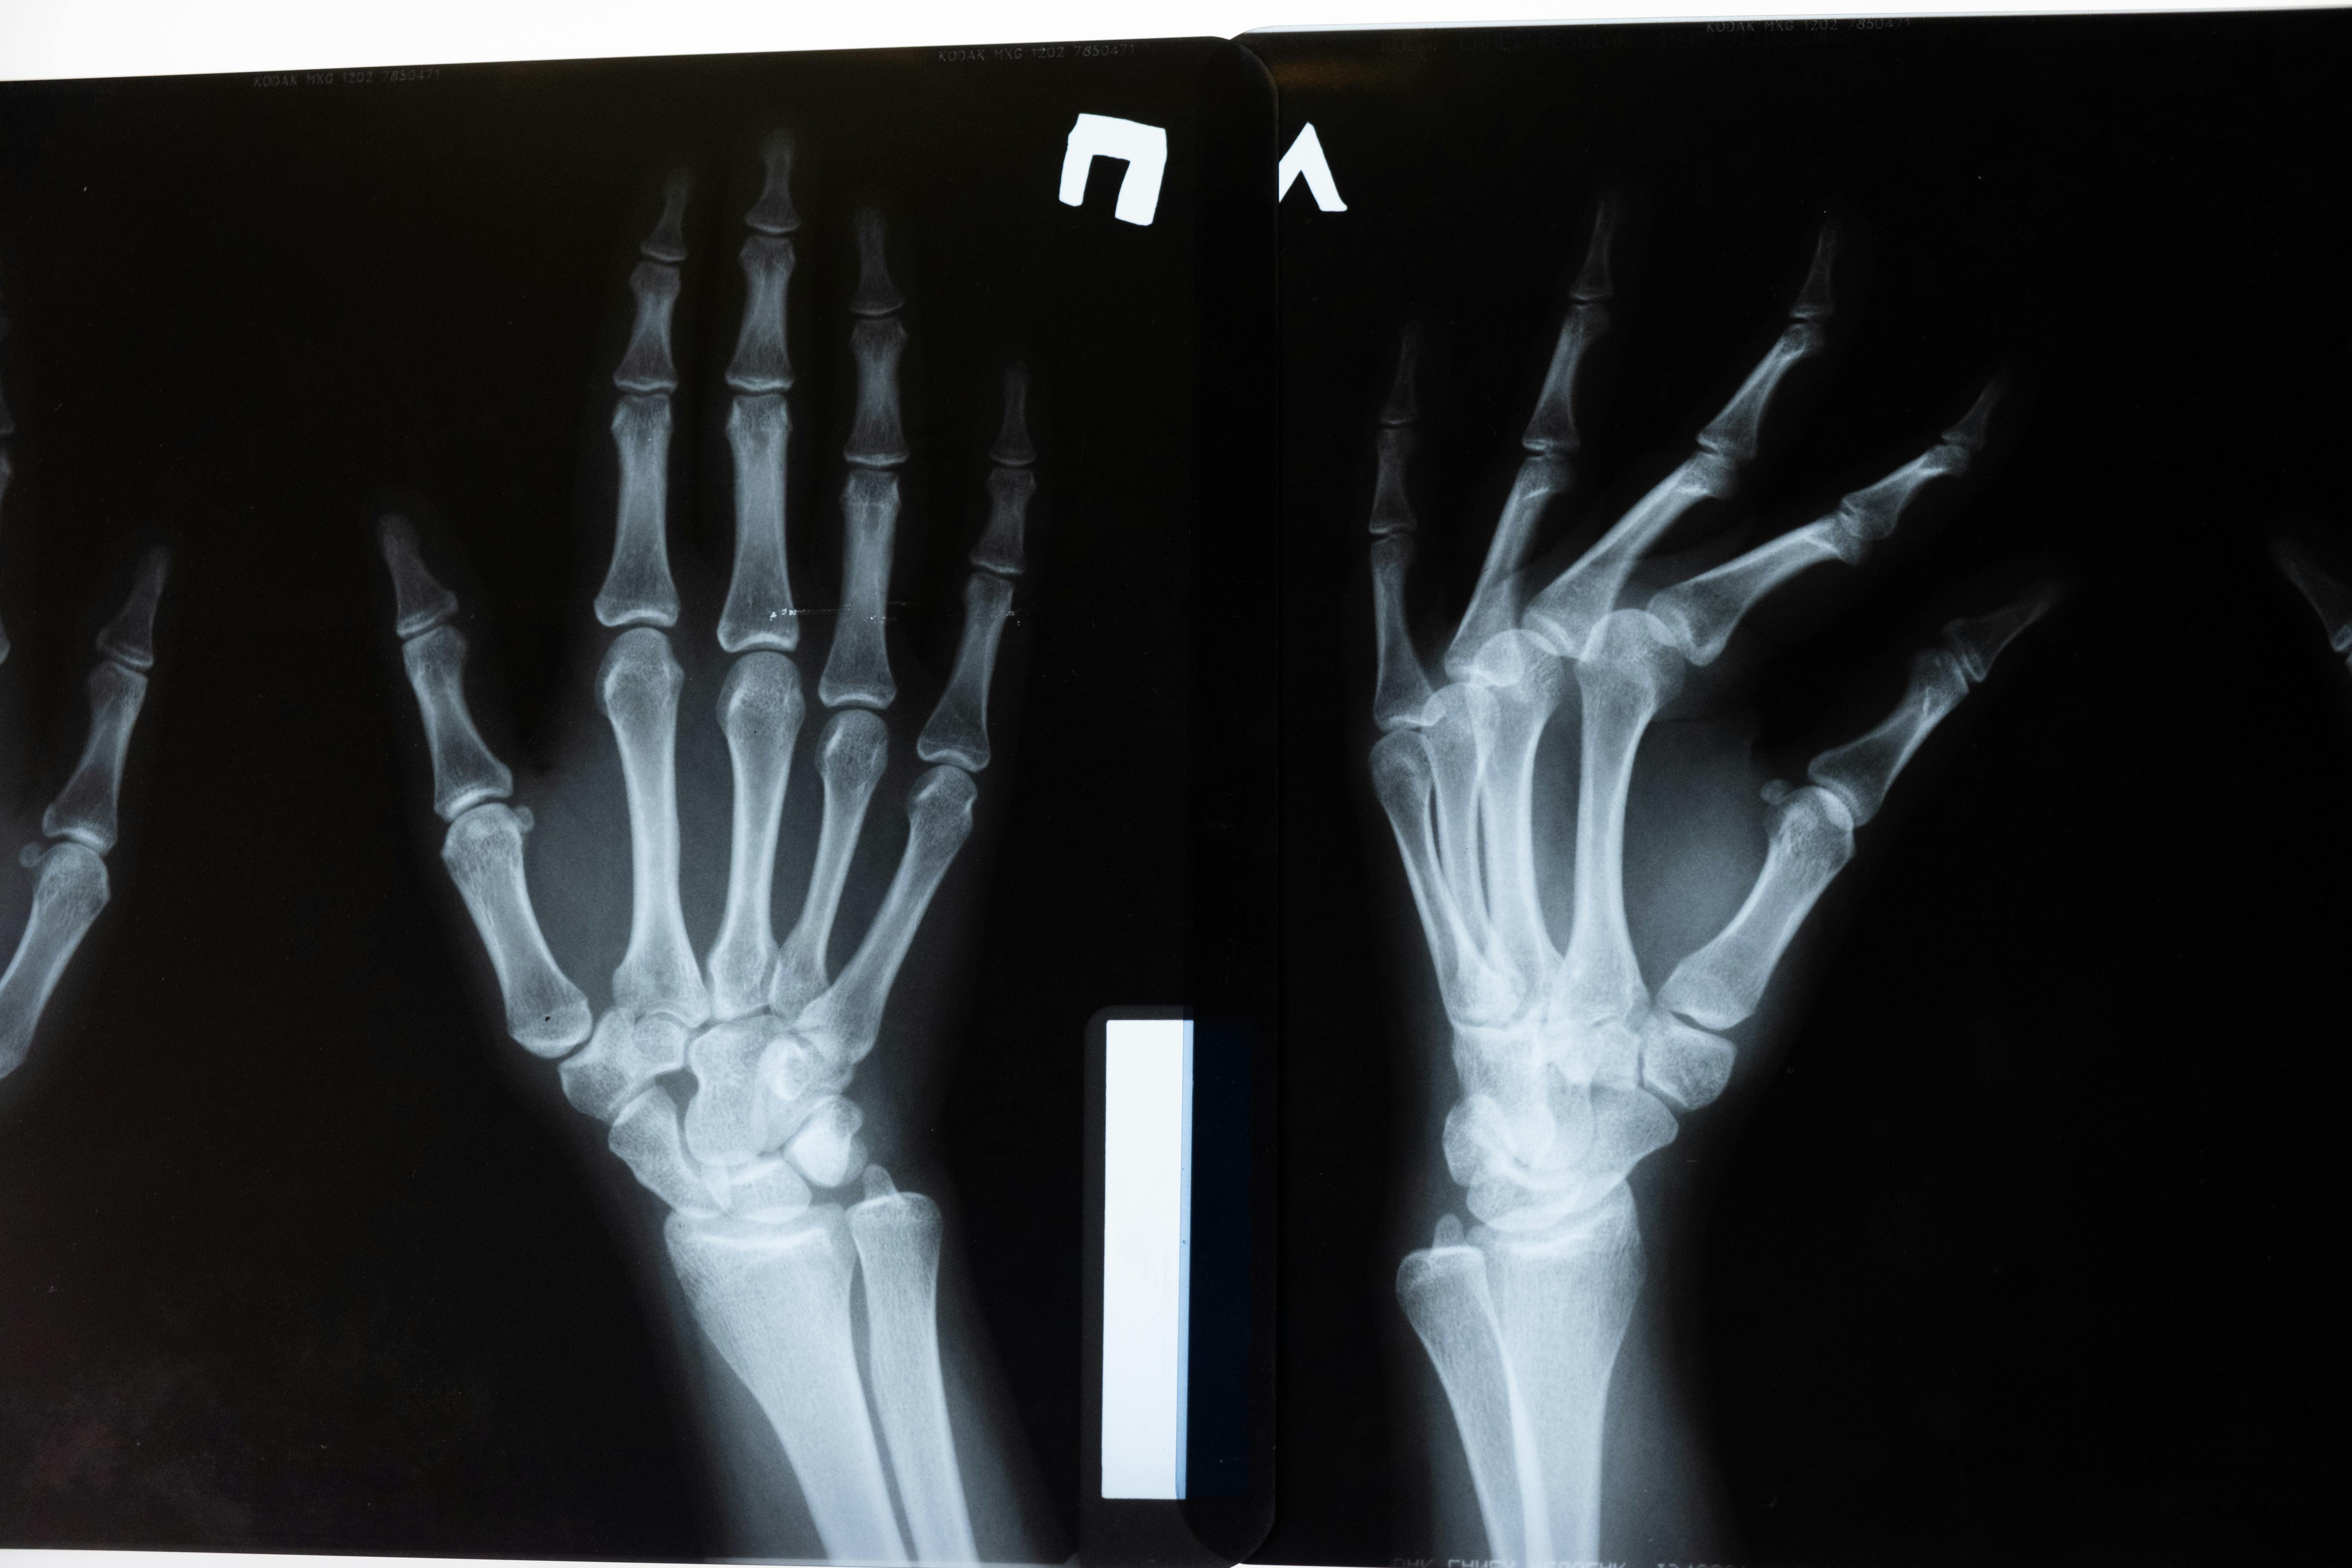

Hypoparathyroidism can weaken bones over time, making them more susceptible to fractures. This occurs because calcium, essential for maintaining strong bones, is drawn from the skeletal system when blood levels are low. The imbalance between calcium and phosphorus further disrupts bone density, leading to a condition known as osteopenia or, in severe cases, osteoporosis. Individuals with hypoparathyroidism may experience frequent bone pain or notice that minor falls or injuries result in fractures. Weight-bearing exercises, adequate calcium and vitamin D supplementation, and periodic bone density scans are crucial for managing this risk. Consulting with a healthcare provider for tailored treatment plans can help improve bone health and reduce the likelihood of fractures.